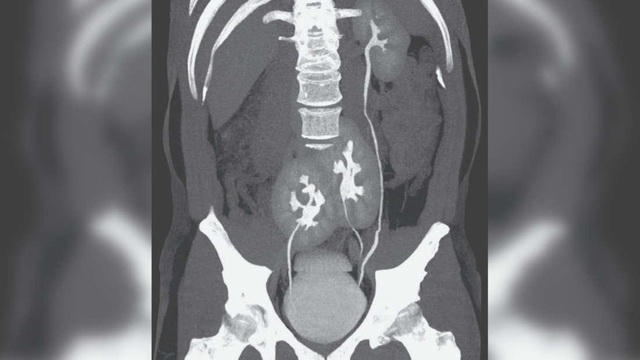

Bệnh nhân 38 tuổi này đã đến một bệnh viện ở thành phố São Paulo của Brazil khi nghi đau thắt lưng do trượt đĩa đệm. Kết quả chụp cắt lớp vi tính (CT) cho thấy người đàn ông đang bị trượt đĩa đệm thực sự. Tuy nhiên, vấn đề này lại không được quan tâm bằng việc các bác sĩ bất ngờ phát hiện ra sự lạ đó là người đàn ông này có tới 3 quả thận. Trong đó, một quả thận trái xuất hiện bình thường và hai quả thận hợp nhất.

"Chúng tôi chưa bao giờ thấy bất cứ điều gì như thế này", tiến sĩ Renato Foresto, một trong những tác giả bài báo cho biết. "Dù ngạc nhiên nhưng chúng tôi lo ngại có vấn đề gì đó với sức khỏe của bệnh nhân”.

Kỳ lạ hơn tình trạng này dường như không ảnh hưởng đến sức khỏe của người đàn ông. Các xét nghiệm máu cho thấy chức năng thận của anh ta bình thường, ngoại trừ đĩa bị trượt, có vẻ mọi thứ vẫn ổn. Bệnh nhân tạm thời được điều trị như bình thường với căn bệnh của mình.

"Chức năng thận của anh ấy hoàn toàn bình thường. Nghiên cứu sâu hơn với siêu âm bụng và chụp cắt lớp được coi là đủ vì nguyên nhân của cơn đau đã được chẩn đoán và không có thay đổi nào khác trong các xét nghiệm trong phòng thí nghiệm", bác sĩ Foresto nói thêm.

Thận của người đàn ông này được xác định là một bất thường bẩm sinh không phổ biến có thể xảy ra trong quá trình phát triển phôi khi một cấu trúc giống như thận nguyên thủy tách ra làm hai. Mặc dù cực kỳ hiếm, tình trạng này đã được ghi nhận một số lần trước đây.